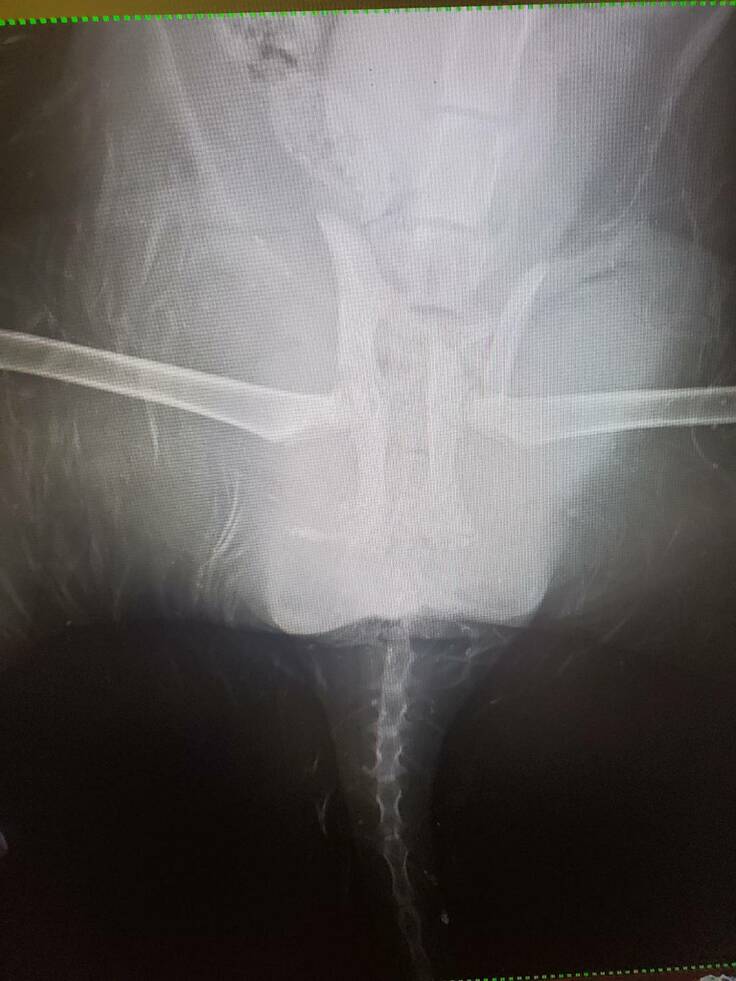

会社の近くを歩いていると猫の鳴き声が聞こえてきました。

4メートルほどの高さのある川を見ると

ずぶ濡れの毎日見かける地域猫がいました。

すぐにハシゴをかけて救出することに。

すると足がぷらぷらで…

自分が仕事中だったため仕事が休みだった彼女に来てもらいすぐに病院に連れて行ってもらうことに。

恐らく車に跳ねられて川に落ちたのだろうと。

結果は両脚の骨折と骨盤の骨折という診断に。

しかし骨盤骨折の手術はかなりの高額との事。